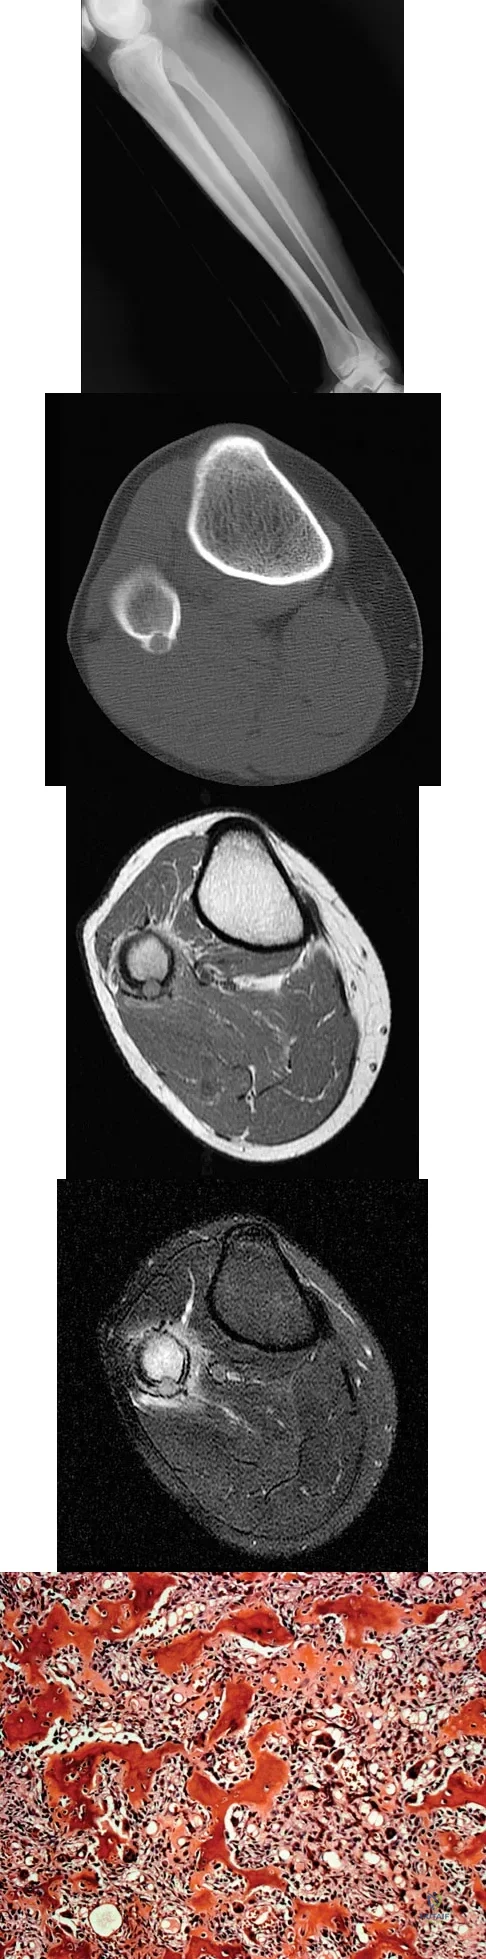

Question 83

Figure 6 shows a sagittal oblique MRI scan. The arrow is pointing to what structure?

Explanation